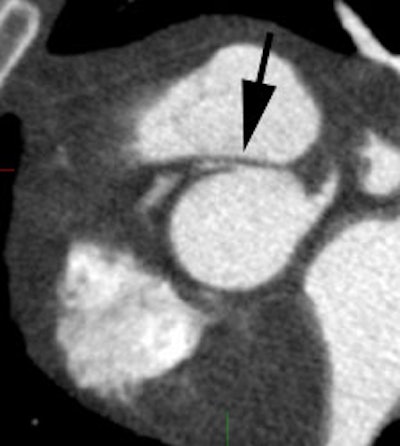

Coronary artery calcification: The patient below has a large calcification in their proximal LAD. Their total calcium score was 537. |

|